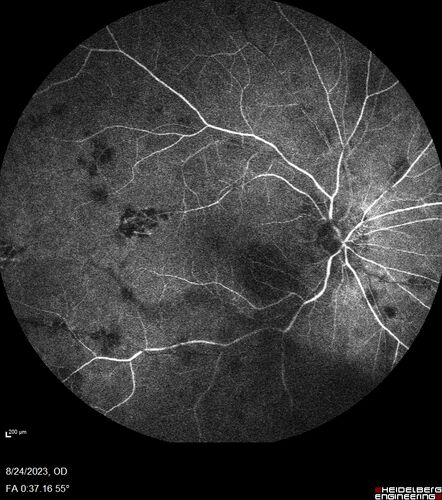

West Nile Virus Multifocal Choroiditis with later CNVM

77 year old female with vision loss in the left eye treated with Anti-VEGF